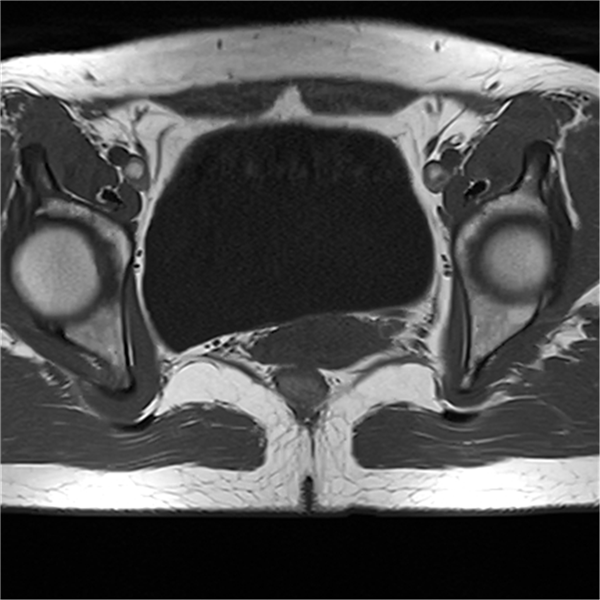

(三)盆腔应用:该设备对于前列腺、直肠、妇科疾病的诊断具有较高的临床应用价值。包括良恶性肿瘤鉴别和相关分期。

部分平扫图像展示